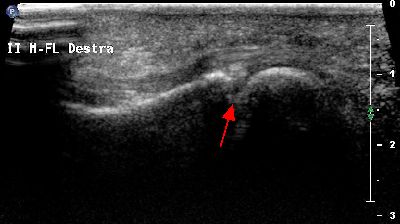

Pannicolo fibrotico intrarticolare

(caso del paziente G.V.)